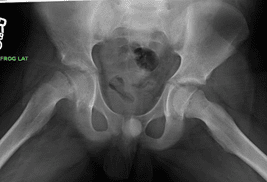

X-rays

X-rays are a key diagnostic tool for visualizing dense structures like bones. To confirm a diagnosis of SCFE, the doctor will request X-rays of your child's pelvis, hip, and thigh from at least two different angles. In cases of SCFE, the X-ray images typically reveal the femoral head slipping off the neck of the femur, a characteristic sign of the condition. These detailed images allow the doctor to assess the severity of the slip and guide appropriate treatment planning.